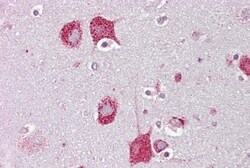

- Immunohistochemistry analysis of brain, cortex tissue using an anti-HEXA polyclonal antibody (Product # PA5-45175).